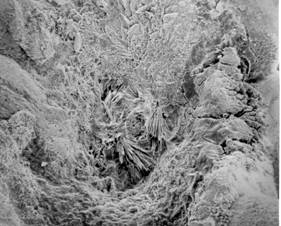

Stébelnaté agregáty močanu sodného,

které se nalézají v krystalizačním jádru whewellitového

kamene. Jádro leží na povrchu v papilární jamce, elektronový mikroskop,

zvětšeno 55x